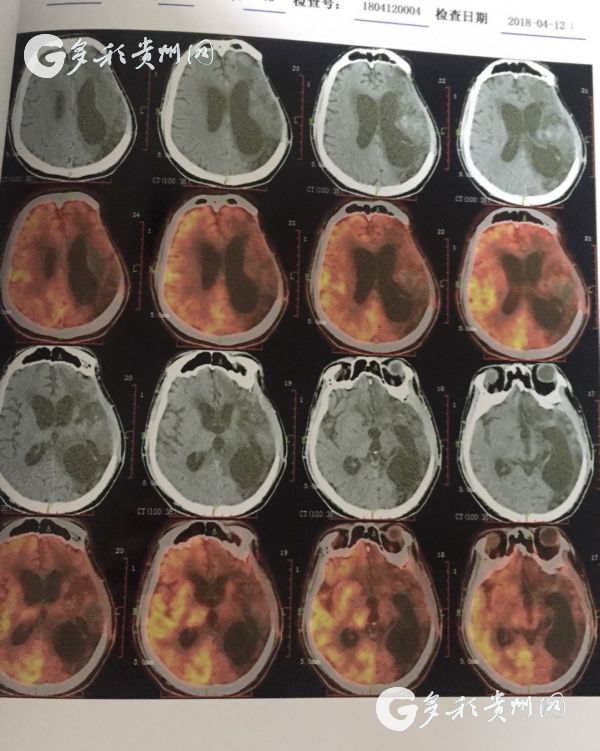

医院提供的患者脑部CT照

据了解,该患者是一位30岁男性,曾因脑出血进行过开颅手术,但术后并发症使病情加重,最后导致长期昏迷,家人最终将其送往太阳成集团tyc33455cc官网附属医院进行治疗。